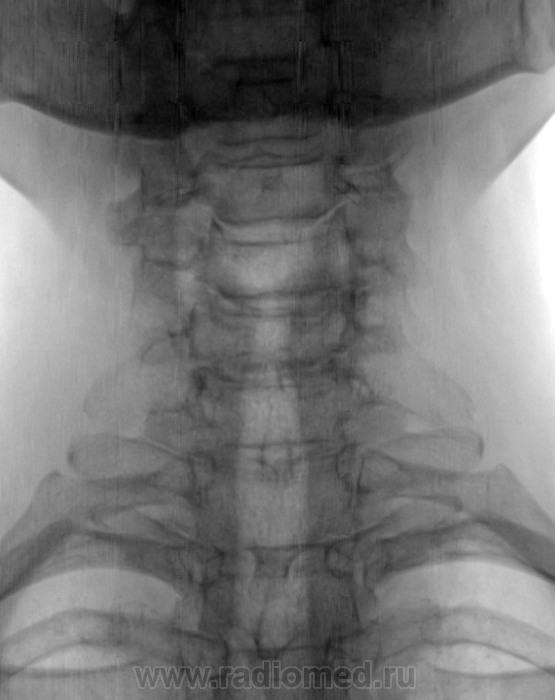

Здесь какой - то подвох? рудиментарные шейные ребра о/хондроз, небольшое смещение С 4 вперед.

а не будет ли сдесь лестничной деформации?+унковертебральный остеохондроз,добавочные шейные рёбра.

Мне задние костные разрастания нижнего угла С4 и верхнего С 5 видятся. И артроз дугоотростчатых суставов добавила бы к выше сказанному.

Обратила внимание на нижний край С6 и С 6-С 7...может придумываю, видно не очень

остеохондроз, III период, шейные ребра, отдельно отметила бы тоже заострение задненижних углов С5 и С6.

Унковертебральный артроз С4-С5. Релистез С5. Остеохондроз С5-С6, С6-С7.